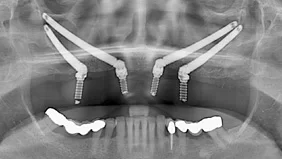

To diagnose, plan and execute your dental implants treatment accurately and in shorter times, our dental clinic has the following equipment: 3D CBCT Extra-oral panoramic X-Ray machine (a Carestream CS 9200 3D Machine), Intra-oral scanners, NAVIDENT, surgical guides, and our own full-equipped CAD/CAM laboratory.